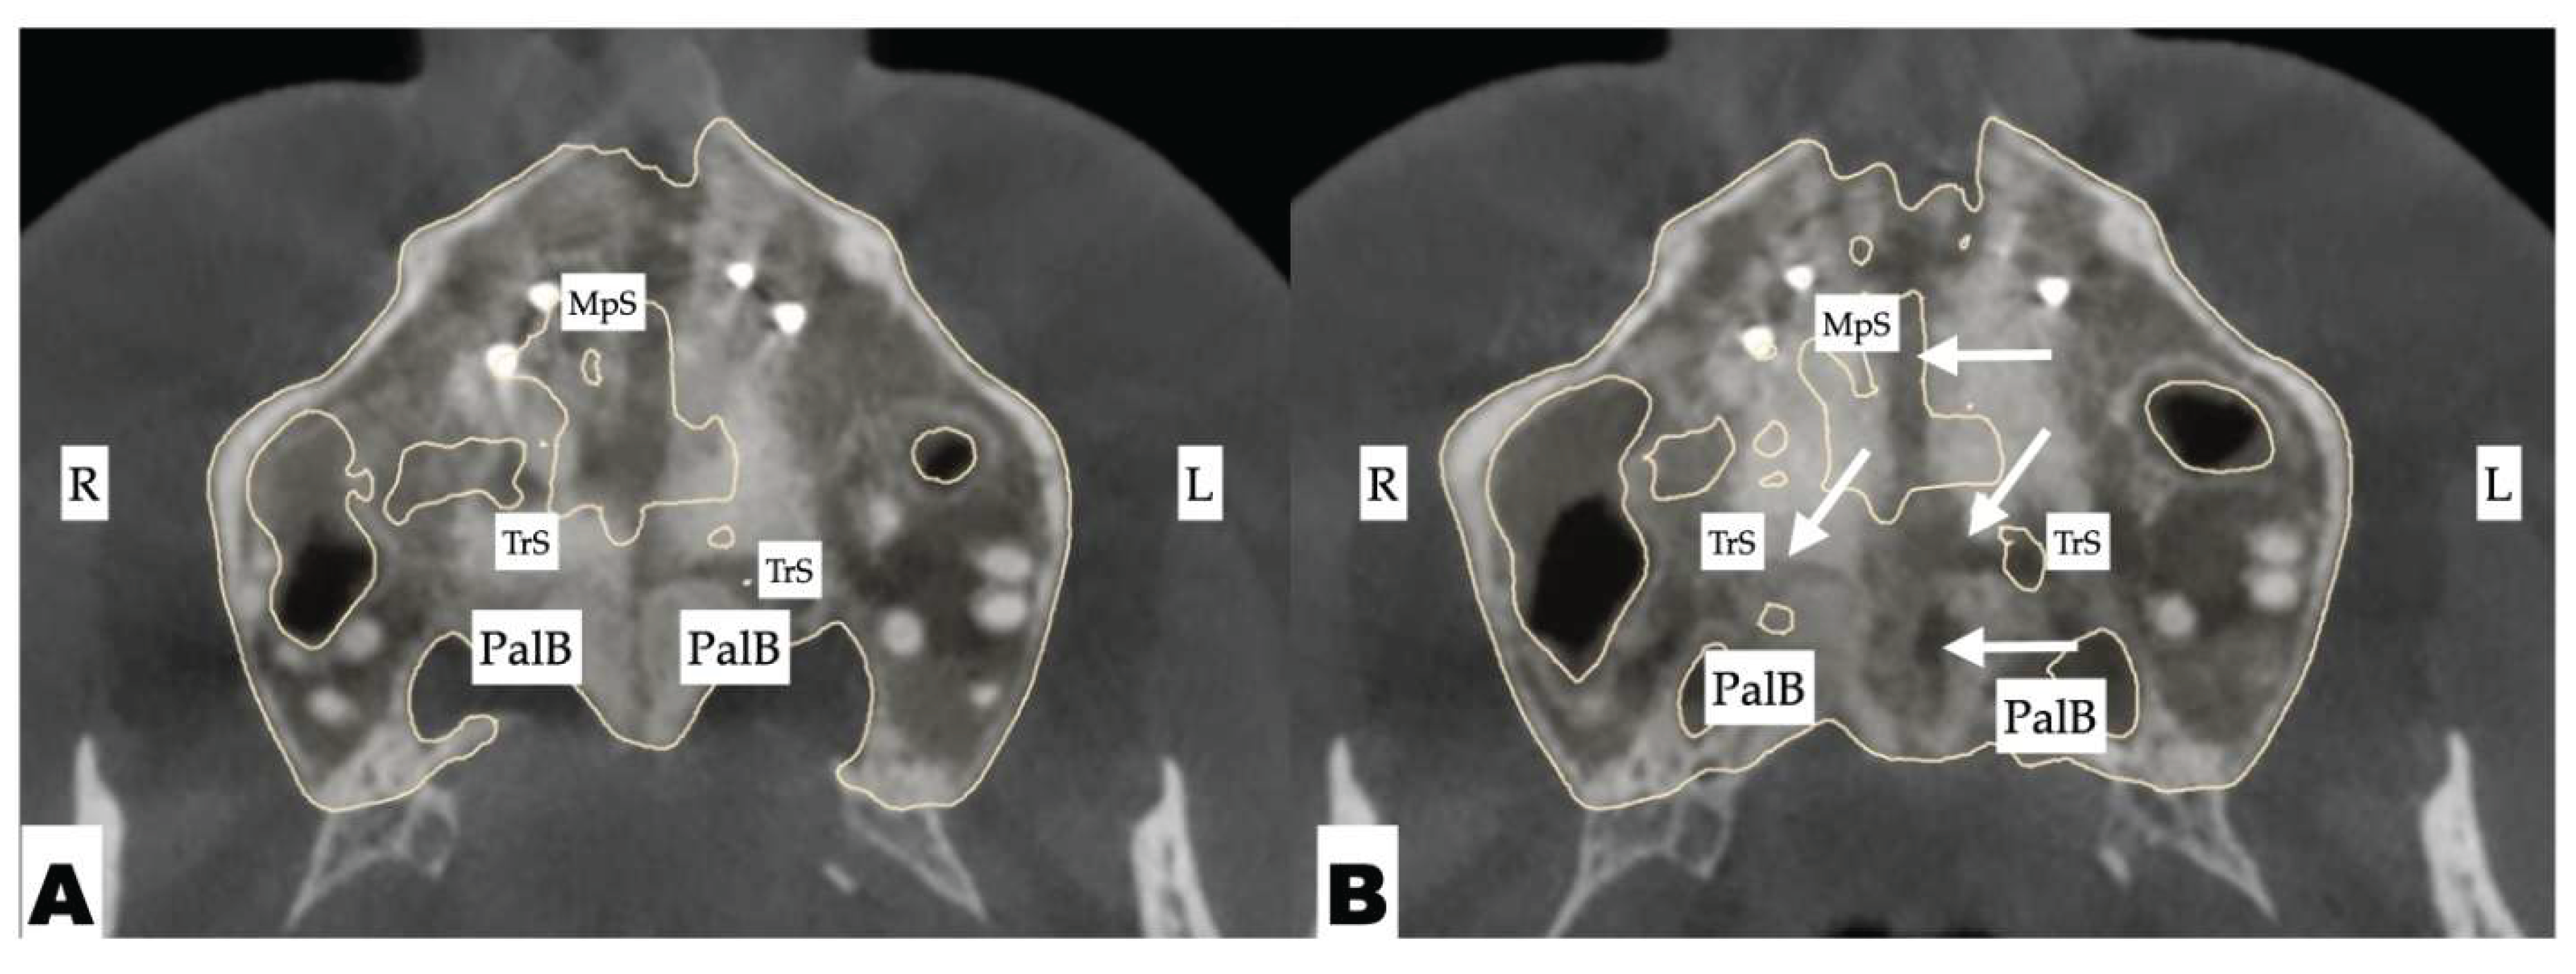

Background: While mini-screw-assisted rapid palatal expansion (MARPE) is effective for correcting maxillary transverse deficiency in adults, perimaxillary suture disarticulation—particularly at the pterygomaxillary junction—can be inconsistent. This study evaluates skeletal and dentoalveolar outcomes of a novel 3D-guided midpalatal piezocorticotomy-assisted MARPE protocol, focusing on expansion symmetry and pre-existing asymmetries. Methods: Three adult patients were retrospectively analyzed after treatment with 3D-guided midpalatal piezocorticotomy-assisted MARPE expansion and one with non-guided midpapalatal piezocorticotomy and MARPE expansion. Surgical guides were digitally designed using CBCT data to align with the nasal septum orientation in multiple planes. Perimaxillary suture disarticulation was measured pre- and post-expansion, and dentoalveolar changes were evaluated. Post-expansion asymmetries were addressed using directly printed aligners. Results: Complete midpalatal suture separation (mean 8.48 mm), involving both anterior and posterior nasal spine regions, was achieved in one patient. Bilateral pterygomaxillary disarticulation averaged 1.06–1.23 mm, resulting in forward–outward rotation of the nasomaxillary complex. Additional separation occurred at the frontonasal (2.03 mm) and vomeromaxillary (1–2 mm) sutures, with no significant changes in orbital or peri-orbital sutures. One patient presented with pre-existing dentoalveolar asymmetry, which intensified the perceived post-expansion imbalance but was successfully corrected with directly printed aligners. In the second case, 5.6 mm of suture separation resulted in a limited lateral nasal width increase (<1.5 mm), while maxillary base expansion exceeded 6 mm. A significant canine plane cant (1.2 mm) and divergent axial inclinations of the maxillary central incisors relative to the palatal plane were also observed. In the second case, a non-impactful palatal bone fracture with asymmetric displacement of the left palatine fragment was documented. After 16 months of aligner therapy, all cases exhibited favorable remodeling of the palatal structures, midpalatal suture, and alveolar processes, accompanied by improved dental alignment, occlusal plane symmetry, and mandibular dentoalveolar adaptation. The dento-alveolar expansion achieved in the third case over the course of 16 months of treatment was approximated at 4 mm. The fourth case showed consistent improvement with direct printed aligners after MARPE midpalatal diasrticulation of 11 mm after experiencing minor bone fracture. Conclusions: Human skulls exhibit considerable variability between the left and right sides, which can influence spatial balance. Pre-existing cranial asymmetries appear to be the primary contributors to asymmetry following MARPE treatment. Careful evaluation of dentoalveolar discrepancies and axial tooth inclinations is essential for preventing and managing potential asymmetric dental arch outcomes during the post-expansion phase. Although peri-maxillary bone fractures are relatively uncommon, their occurrence is influenced by multiple factors. Adjunctive techniques, such as 3D-guided midpalatal piezocorticotomy, show promise in significantly lowering the risk of intra-expansion peri-maxillary fractures.

| Suture nomenclature | Amount of disarticulation |

|---|---|

| Midpalatal | 8.48 mm |

| Palatinomaxillary (transverse) | none |

| Nasomaxillary | 1-2 mm |

| Zygomaticomaxillary | none |

| Lacrimomaxillary | none |

| Ethmoidomaxillary | none |

| Sphenomaxillary | none |

| Vomeromaxillary | 1-2 mm |

| Frontomaxillary | 2.5 mm |

| Pterygomaxillary | 1.06-1.23 mm |

| Frontonasal | 2.03 mm |

| Frontozygomatic | None |